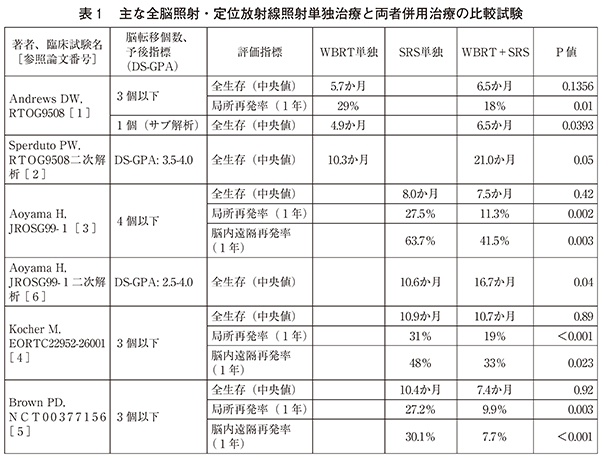

非小細胞肺がんの脳転移における全脳照射の意義は がん情報サイト

Https Hosp Gifu U Ac Jp Center Gan Img 30 Cb01 Pdf

Https Hosp Gifu U Ac Jp Center Gan Img 30 Cb01 Pdf